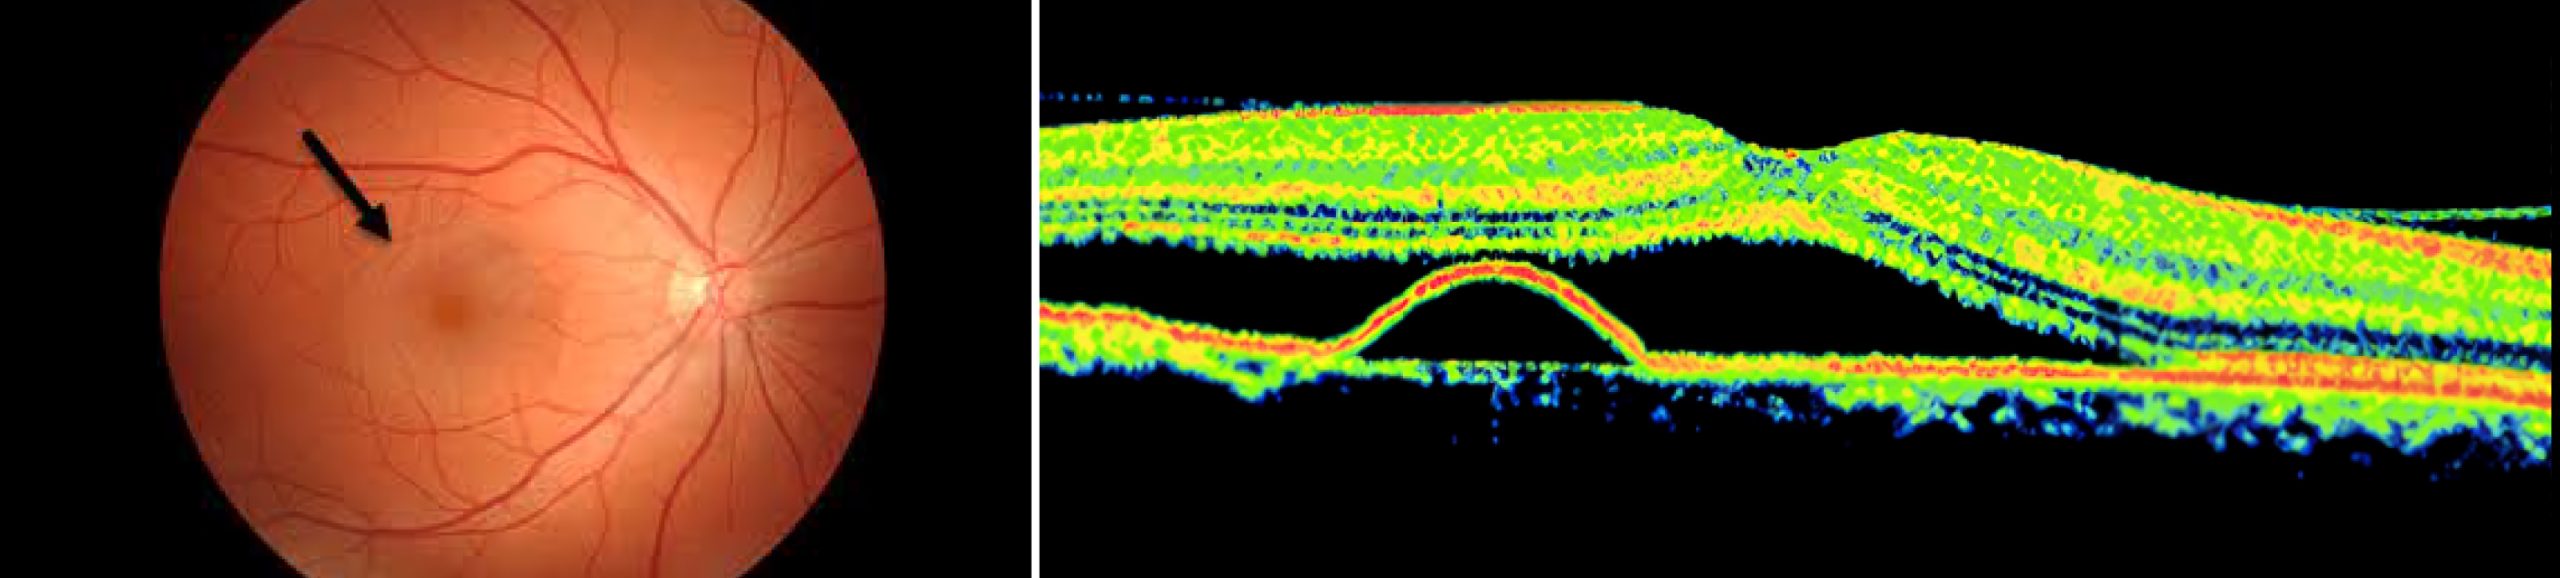

视网膜静脉阻塞

(CRVO / BRVO)

视网膜中央静脉阻塞 (CRVO) 是一种常见的出血性眼底疾病,中医称为“络瘀暴盲”,主要影响中老年人,其特征是视网膜中央静脉(负责引流视网膜血液的主要静脉)发生阻塞。这种阻塞导致血液和液体积聚,引起视网膜肿胀和损伤,通常导致单眼突发性、无痛性视力丧失。CRVO与视网膜分支静脉阻塞 (BRVO) 一样,病因和发病机制复杂,包括高血压、糖尿病、青光眼和血液凝固障碍等风险因素。它分为缺血性(严重)和非缺血性(较轻)两种类型。最常见的并发症是黄斑囊样水肿,导致明显的中心视力丧失,严重情况下还会导致视网膜新生血管形成、玻璃体出血和新生血管性青光眼,最终导致失明。诊断需要进行全面的眼科检查,包括眼底照相和光学相干断层扫描 (OCT)。控制疾病的重点是管理并发症,使用抗VEGF注射、激光疗法或皮质类固醇,同时监控高血压、糖尿病和炎症等原发疾病,并避免吸烟等风险因素。

中医 (TCM) 认为该病与肝气郁结、肝肾阴虚、内生湿痰和血液循环问题有关,主张采用疏肝理气、滋补肝肾、健脾祛湿、活血化瘀通络的调理方法。现在临床上,中西医结合处理该病也流行。

中心性浆液性脉络膜视网膜病变 (CSC)

中心性浆液性脉络膜视网膜病变 (CSC) 是一种眼部疾病,其特征是视网膜下方,特别是黄斑区域的液体积聚,导致中央视力模糊或扭曲。这种情况的发生是由于脉络膜血管通透性增加,继而导致视网膜色素上皮 (RPE) 的继发性损伤和视网膜神经上皮的局部脱离。虽然确切病因通常未知,但压力和皮质类固醇的使用是常见的风险因素。CSC主要影响中青年男性,通常单眼发病,虽然常常可自行消退,但易于复发,且可加重损害视力。临床表现包括不同程度的视力下降、视物变形、视物变小和中心暗点。眼底检查显示圆形或椭圆形的脱离,伴有清澈或浑浊的液体,可伴有视网膜下沉积物和小的浆液性RPE脱离。西医侧重于降低脉络膜通透性、封闭RPE渗漏和促进液体吸收,采用激光光凝或光动力疗法等方法。早期发现和定期监测对于管理CSC和保护视力至关重要。

中医将此病称为“视瞻有色”,认为其发病原因复杂,可能与以下因素有关:过度思虑导致脾胃功能失调,水湿停滞;情绪不畅,肝气郁结,郁而化热,湿热上扰;或肝肾亏虚,精血不足,眼睛失养。中医中药在处理此病具有一定的优势,但疗程较长,从开始用药到炎症消退并形成瘢痕,可能需要半年以上。然而,部分患者病情迁延不愈,视力明显下降,需要积极进行西医治疗。